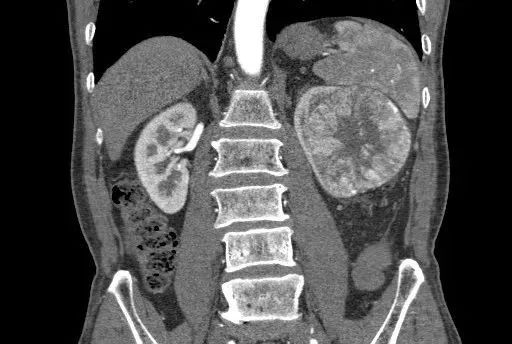

嗜酸细胞腺瘤。男,63 岁。不规则较大瘢痕。瘢痕完全填充式强化。